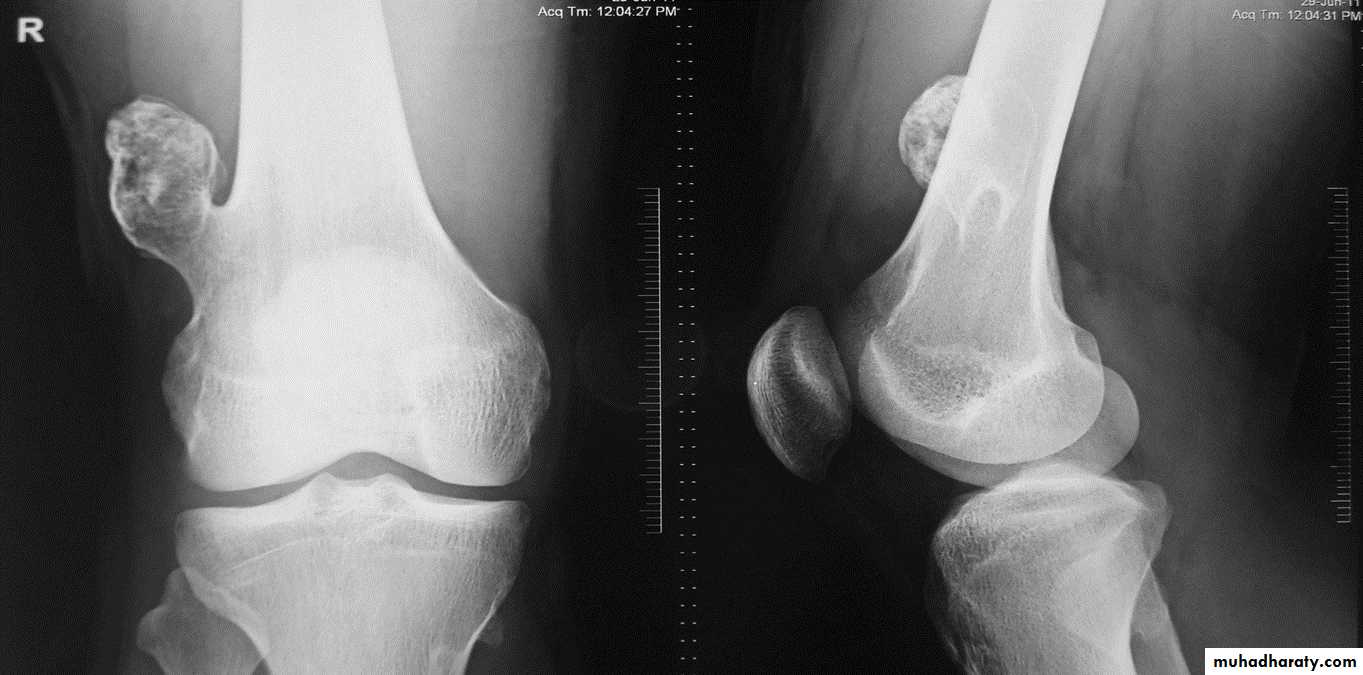

OSTEOCHONDROMA (EXOSTOSIS)

Cartilage-covered bony projection (exostosis) on the external surface of a bone.Most common benign bone lesion. Osteochondromas have their own growth plate

and stop growing with skeletal maturity.

Age: < 20 years (adolescence)

Location: most commonly (85%): tibia, femur,

humerus.

Radiographic features:

Two types:

* Pedunculated: slender pedicle directed away from growth plate

* Sessile (broad base)

Characteristic findings:

* Continuous with parent bone:Uninterrupted cortex

Continuous medullary bone

* Calcification in the chondrous portion of cap; may be cauliflower-like

* Metaphyseal location (cartilaginous origin)

Lesion grows away from joint

Osteochondroma of the distal femur.

The cortex is continuous with that of the underlying bone and trabecular bone merges with that of the femur. A well-defined cartilage cap contains calcification and is directedaway from the joint.

Diaphyseal aclasia.

Multiple osteochondromasEnchondroma :